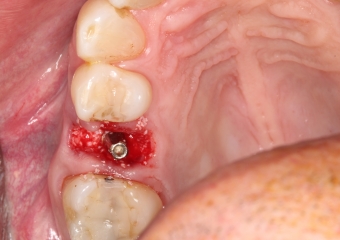

Extração - Implante imediato

Implante - Enxerto ósseo sintético